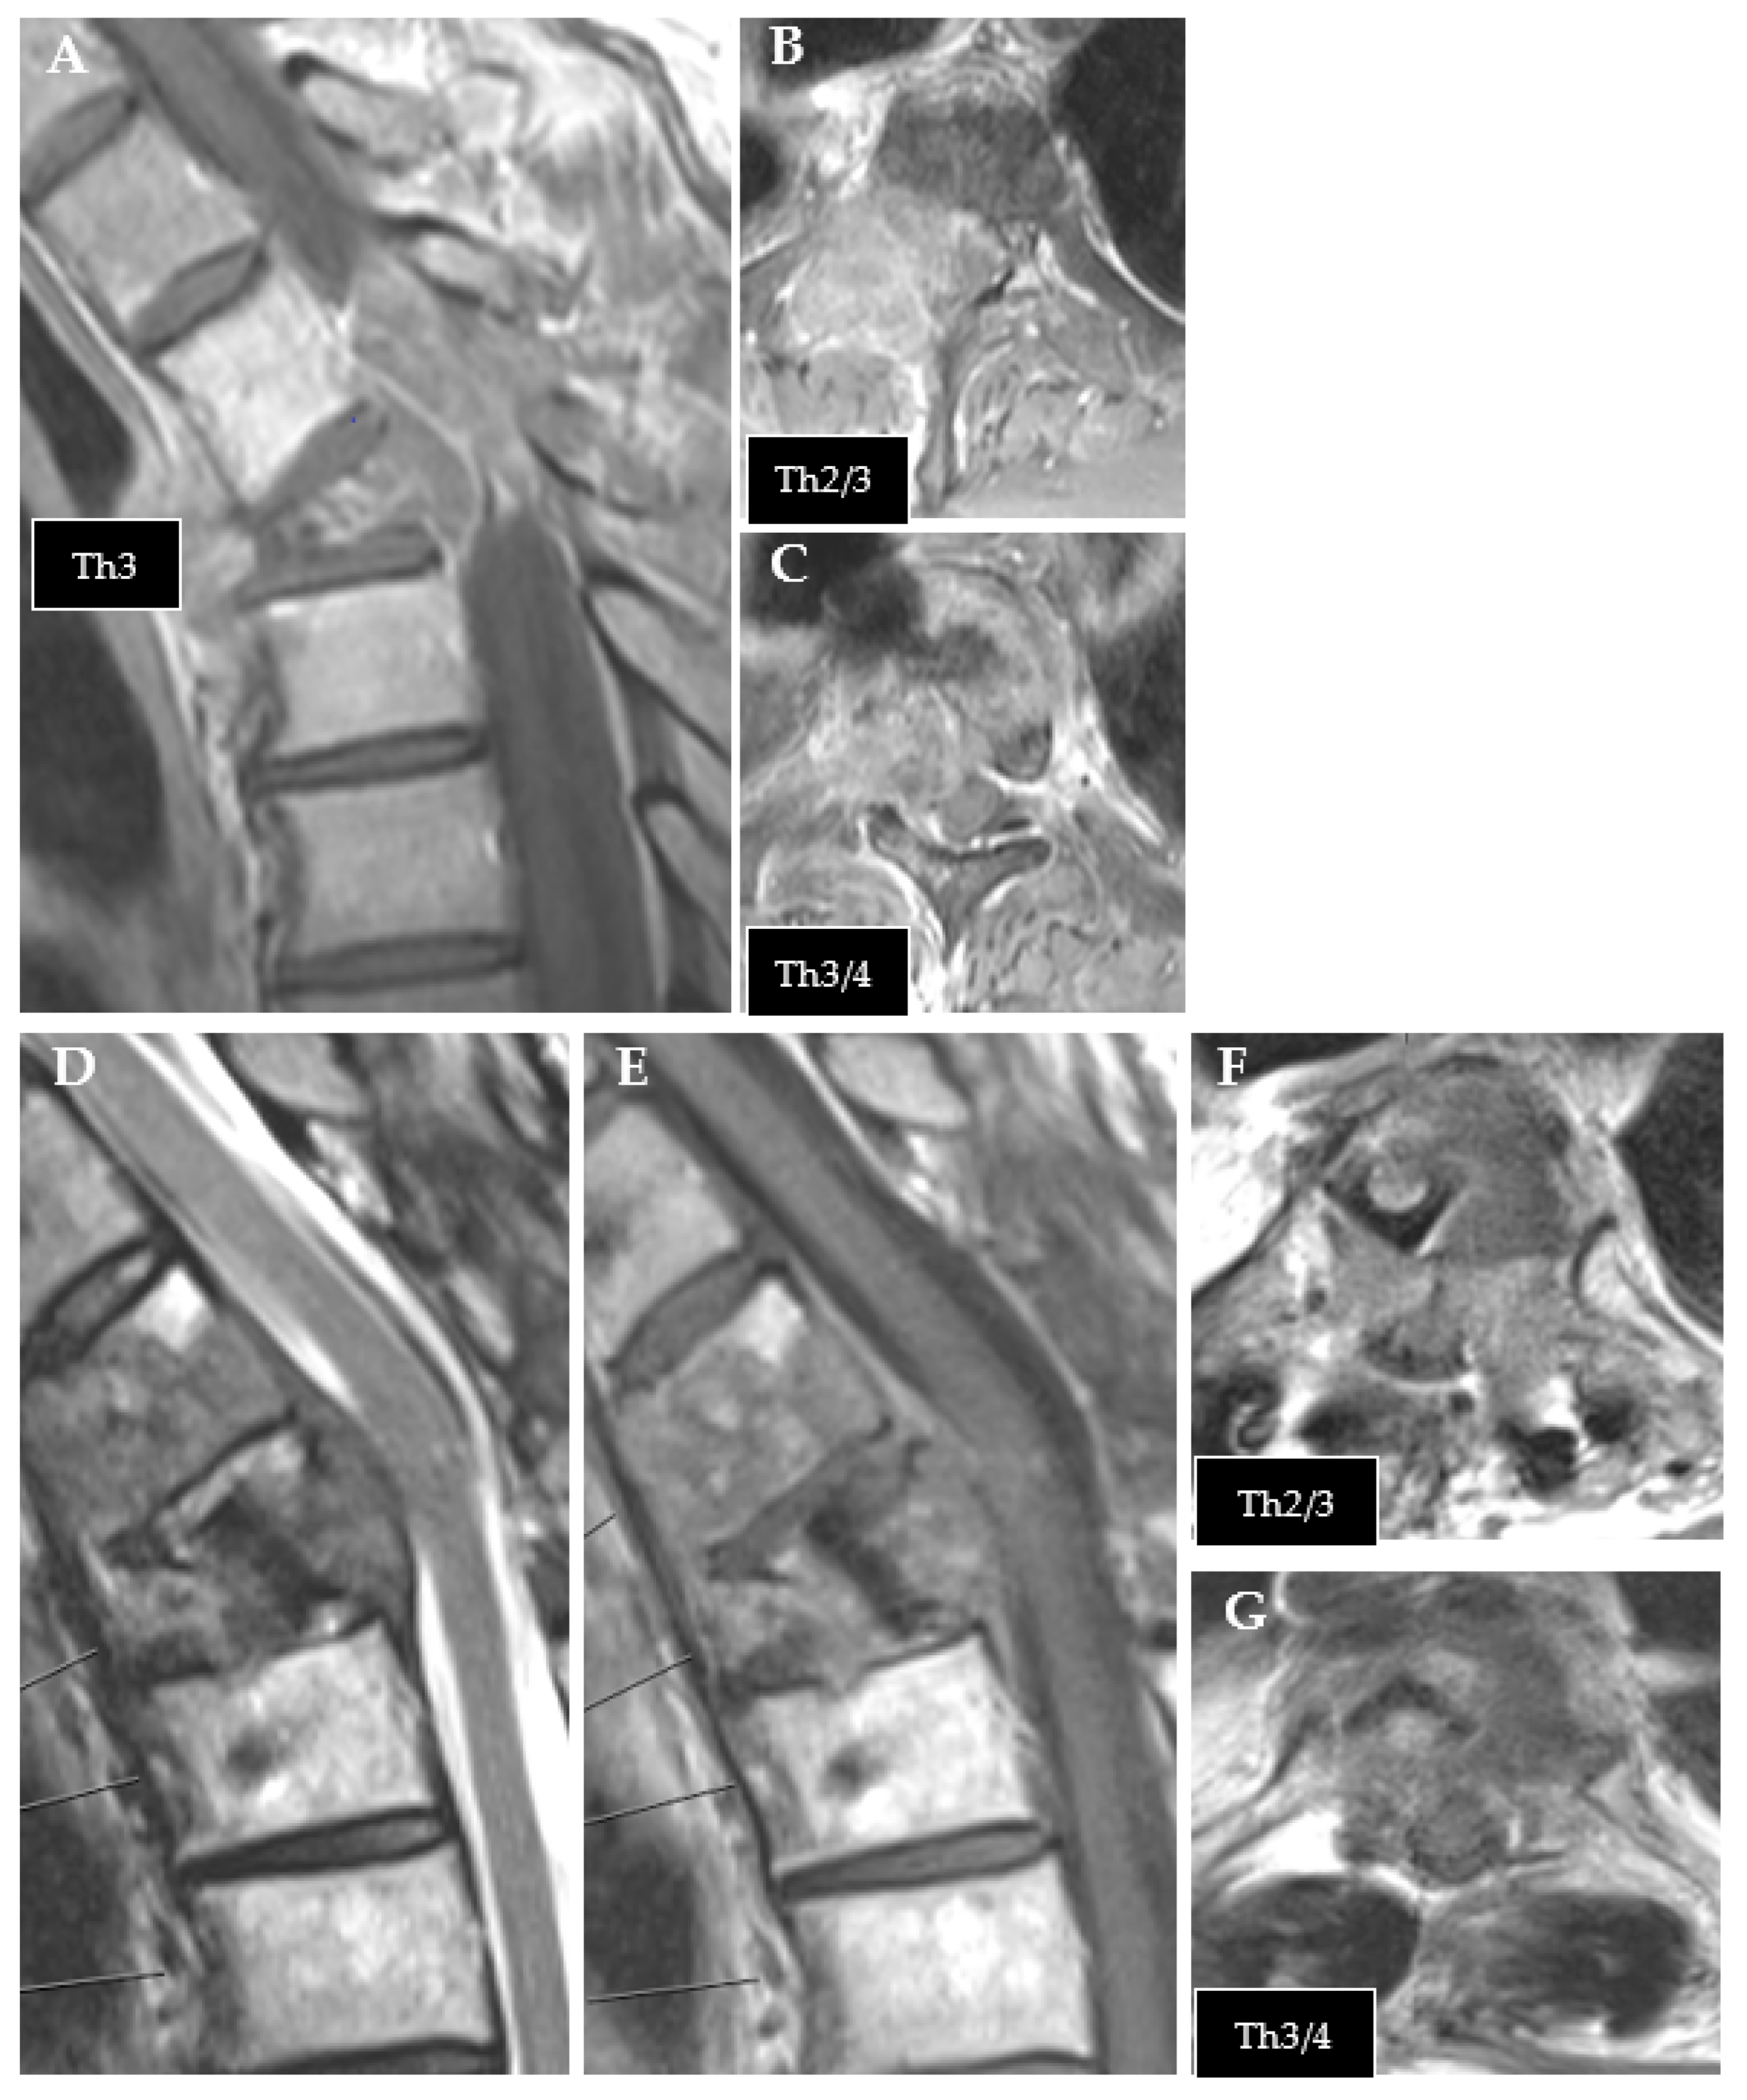

Figure 1.

Exemplary case of tumor recurrence. (A–C): preoperative MRI of thoracic metastasis from urothelial carcinoma (T1 contrast enhanced). (D–G): follow-up MRI after CFR-PEEK instrumentation showing tumor recurrence ((D): T2; (E–G): T1 contrast enhanced).